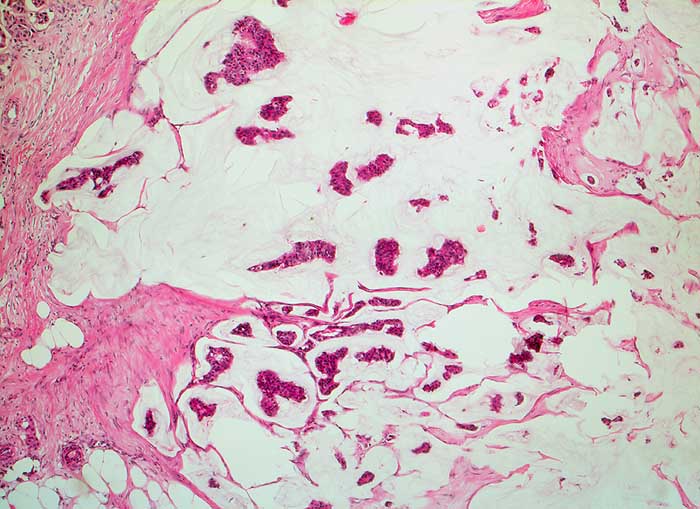

Einleitung

Homogene oder schlierenförmige extrazelluläre Schleimmassen mit Inseln von Tumorzellen mit geringen Kernatypien sind pathognomonisch für das muzinöse Mammakarzinom. Die Zellzahl ist meist nicht sehr hoch. Die Zellen liegen einzeln oder in kleinen kugeligen oder pseudopapillären Verbänden. Der Schleim erscheint in der Pap Färbung blau-grau bis rötlich. Siegelringkarzinome zeigen grössere intrazytoplasmatische Schleimvakuolen.

Unten werden zwei Beispiele von typischen muzinösen Karzinomen gezeigt.